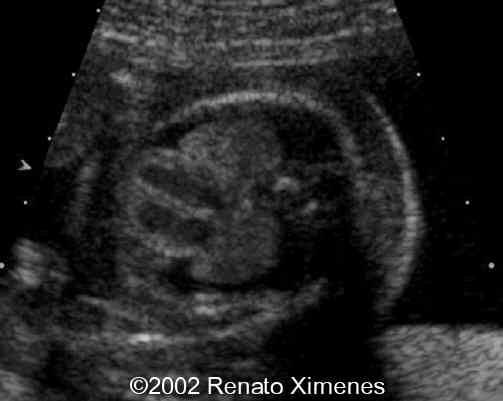

This second trimester fetus demonstrates a very thick nuchal edema with cystic hygroma:

case0072-1

case0072-2